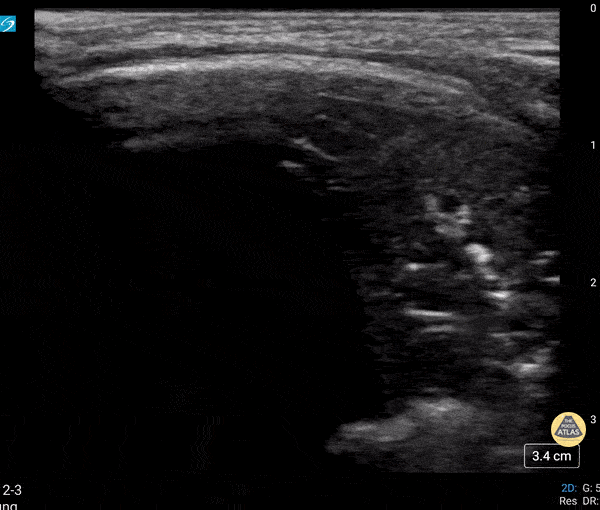

Peds-Lung - Dynamic Air Bronchograms

Neonate in respiratory failure status post intubation. The presence of dynamic air bronchograms helps point away from atelectasis. Contributor: Peter Gutierrez, MD, FAAP | Emory University School of Medicine/Children's Healthcare of Atlanta | @pocuspete